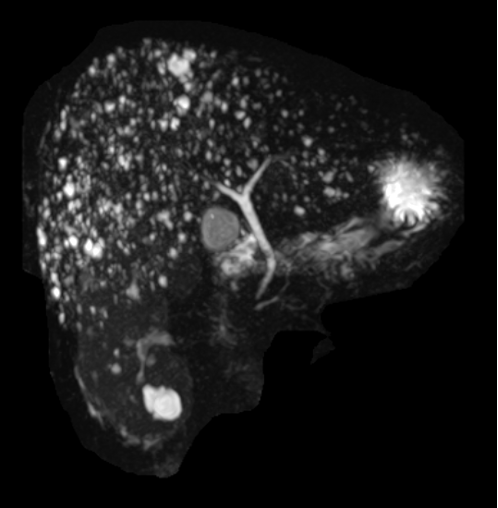

肝脏磁共振见弥漫分布小圆形信号,呈“满天星样”

胆管错构瘤是一种较为罕见的肝脏良性病变。该病变主要发生在肝脏的胆管系统中,由正常组织的异常组合构成,不同于真正的肿瘤,它们不具有侵袭性或转移性。胆管错构瘤通常在影像学检查中偶然发现(如图),由于其临床表现不明显,诊断和处理具有一定的挑战性。

胆管错构瘤的诊断主要依赖于影像学检查。超声检查是一种常用的无创检查方法,可以发现肝脏内多发的低回声小囊性病变。然而,由于超声检查的分辨率有限,其特异性不高,容易与其他肝脏囊性病变混淆。因此,对于疑似胆管错构瘤的患者,建议进行进一步的CT扫描或MRI检查。

CT扫描可以清晰地显示肝脏内病变的形态、大小和分布,有助于与其他肝脏囊性病变相鉴别。MRI检查则具有更高的分辨率和软组织对比度,能够更准确地评估病变的性质和范围。在某些情况下,如果影像学检查无法明确病变的性质,可能需要进行肝脏穿刺活检以排除其他病变。